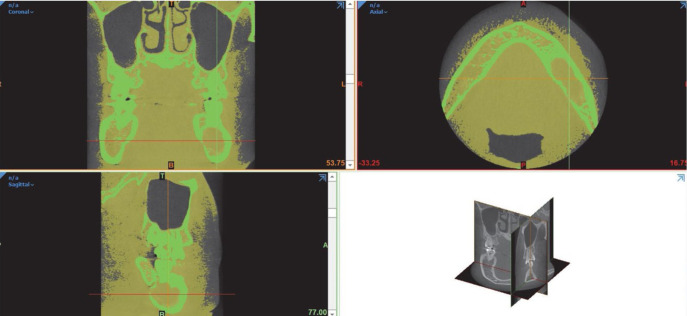

目的:本研究旨在利用锥束计算机断层扫描(CBCT)进行三维容积分析,探讨影响牙源性囊肿减压术后缩小率的潜在因素:研究样本包括 2010 年至 2022 年期间在朱拉隆功大学牙科学院口腔颌面外科接受牙源性囊肿减压术的 41 名患者的 CBCT 图像。研究人员收集了术前和术后的 CBCT 结果,并进行了体积分析,以评估基于不同参数的囊肿病变缩小率和体积缩小百分比的差异。对这些参数之间的相关性进行了分析,以确定其关联性:结果:在这项研究中,牙源性囊肿的平均减压时间为 316 天。男性的减压率高于女性(PPC结论:对牙源性囊肿减压率的了解可以帮助我们更好地了解牙源性囊肿:了解牙源性囊肿的缩小率对于外科医生评估去核手术前的减压时间和确定最终治疗方案至关重要。性别和初始病变体积对缩小率有显著影响。

Purpose: This study aimed to investigate the potential factors that could affect the reduction rate of odontogenic cysts following decompression using cone-beam computed tomography (CBCT) for 3-dimensional volumetric analysis.

Materials and methods: The study sample consisted of CBCT images of 41 individuals who underwent decompression of odontogenic cysts at the Department of Oral and Maxillofacial Surgery, Faculty of Dentistry, Chulalongkorn University, between 2010 and 2022. Preoperative and postoperative CBCT results were collected, and a volumetric analysis was conducted to evaluate the differences in the reduction rate and the percentage of volume reduction of cystic lesions based on different parameters. Correlations between these parameters were analyzed to determine associations.